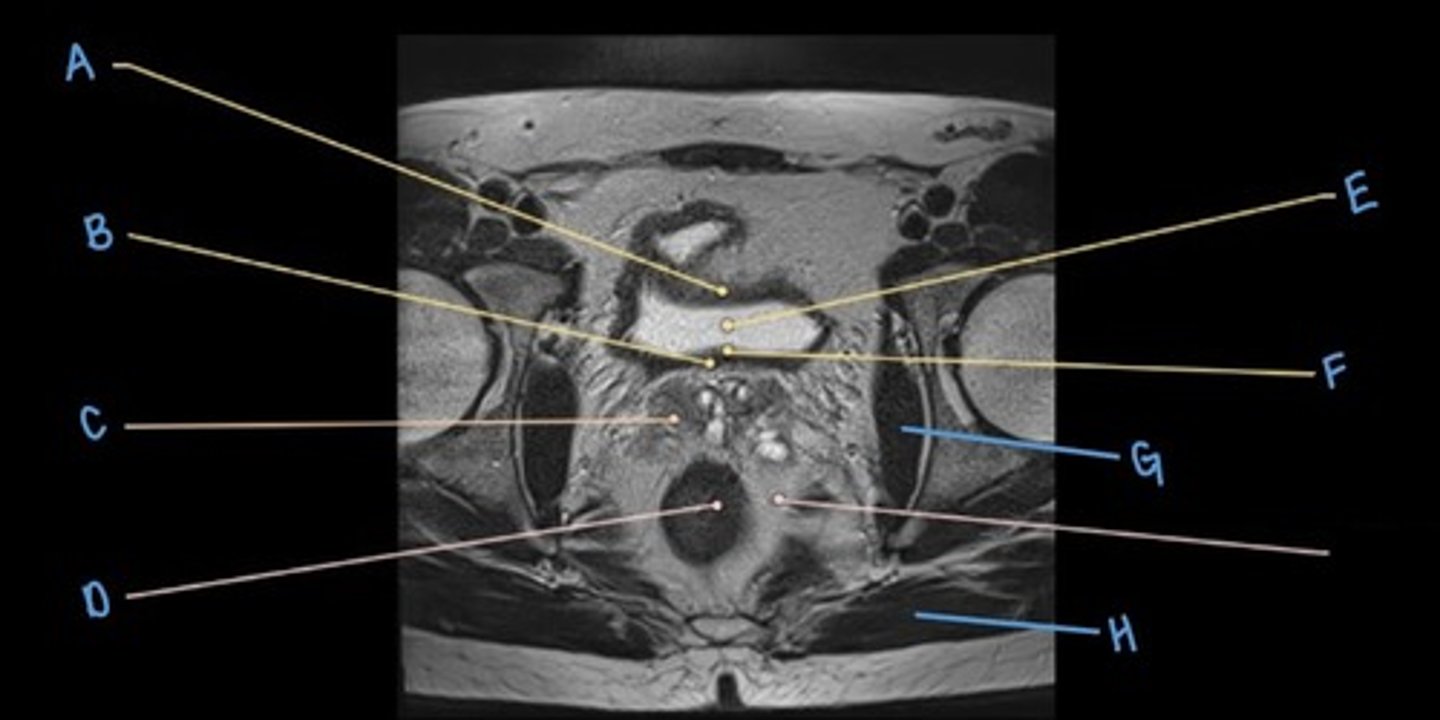

ureter

A & F

small intestine

B

bladder

C

prostate

D

sigmoid colon

E

iliacus muscle

G

psoas major muscle

H